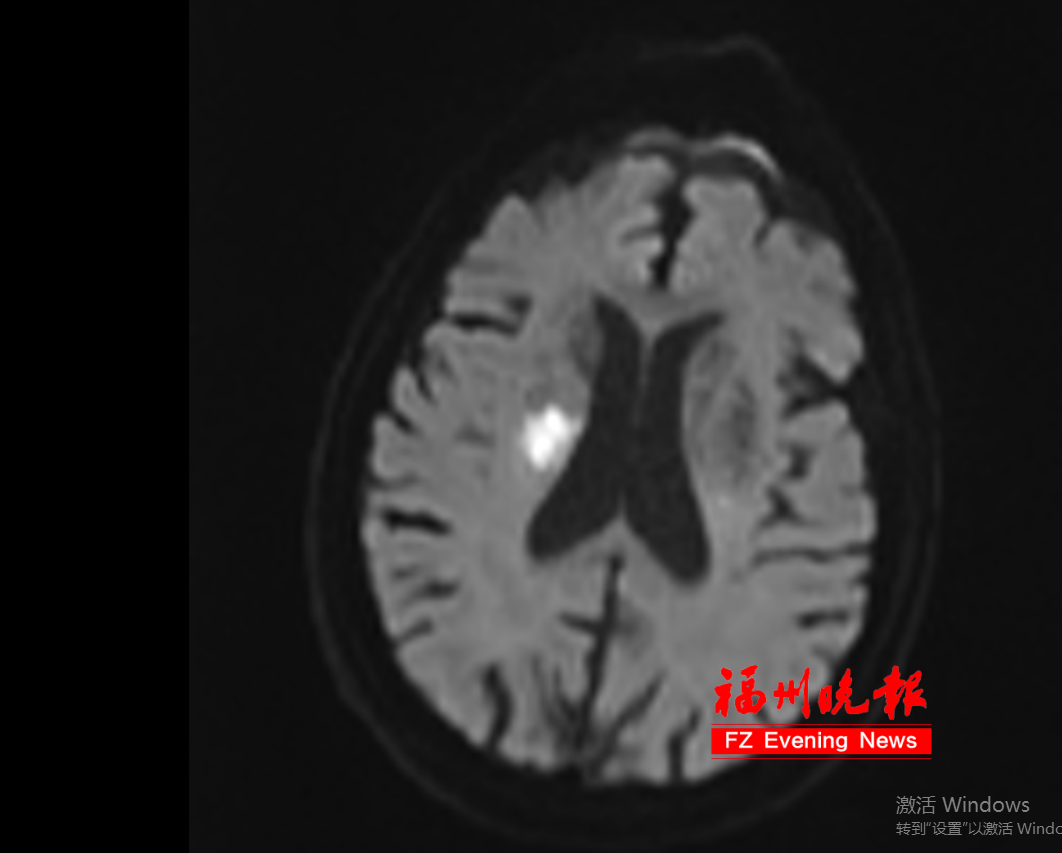

通过头颅CT检查,医生确诊张大叔患上了急性脑梗死。幸好送医及时,医生立即实施了静脉溶栓治疗。